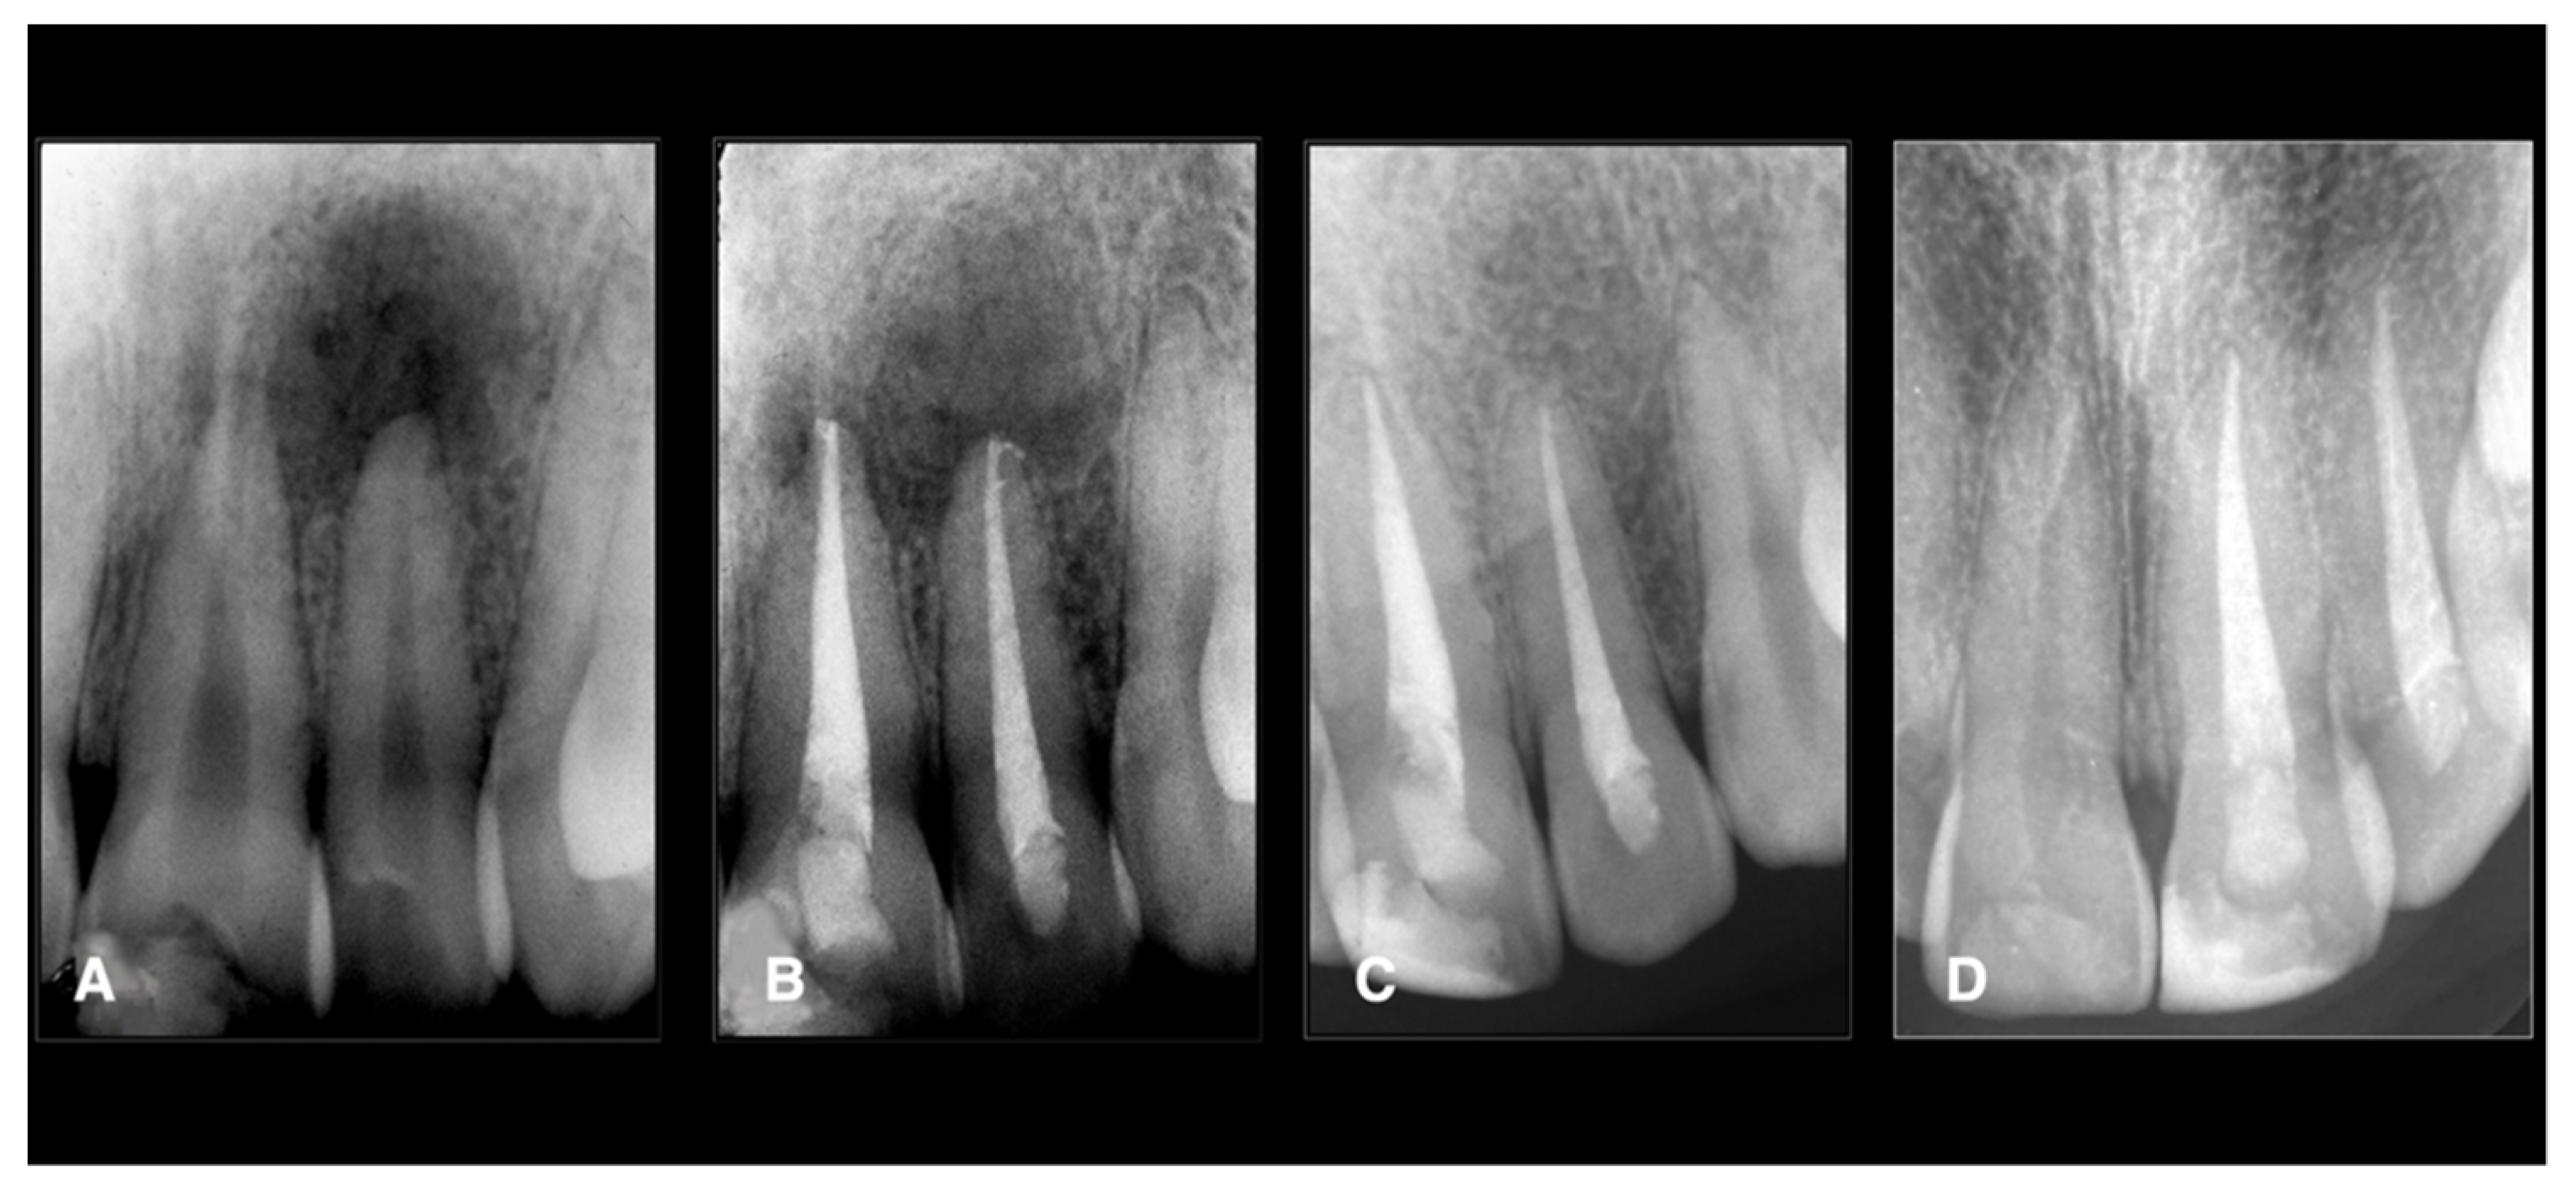

The four failed teeth were two maxillary premolars and two mandibular molars (these teeth did not have sealer extrusion). One maxillary premolar failed because of a vertical root fracture (Figure 1 and Figure 2) (Appendix A).

Figure 2.

Endodontic treatment of a second maxillary left incisor. The tooth was necrotically associated with periapical lesions. The treatments were done using conservative shaping and the 3D cleaning procedure, as mentioned in the Materials and Methods. (A) Preoperative X-ray, (B) postoperative X-ray, (C) 1-year follow-up, (D) 2-year follow-up showing healing.